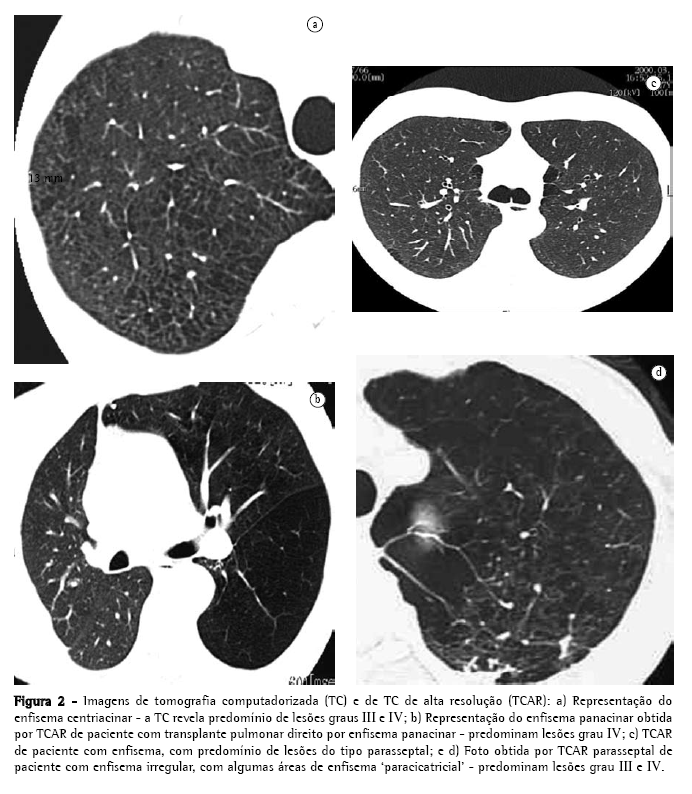

Em 1958,(13) publicou-se um artigo de grande importância por apontar erros na preparação dos espécimes pulmonares para entendimento das lesões enfisematosas, descrevendo melhores técnicas de distensão e fixação. Em revisão de trabalhos anteriores,(6) uma autora assim definiu os parâmetros anatomopatológicos, conforme sua distribuição em relação ao ácino, (Figura 2): centroacinar, parasseptal ou periacinar, panacinar, e irregular.

O tipo centroacinar, como o nome sugere,acomete a porção central do ácino, junto aos bronquíolos respiratórios. Há dilatação seletiva, com confluência dos elementos centrais no ácino, principalmente os bronquíolos respiratórios e seus alvéolos. O processo tende a ser mais acentuado nos terços superiores dos lobos superiores e inferiores. O enfisema centroacinar está fortemente associado ao tabagismo e à bronquite crônica, com predomínio no sexo masculino. As alterações inflamatórias nas pequenas vias aéreas são comuns, com entupimento, infiltrado mural e fibrose, levando a estenose, bloqueio do fluxo de ar, além de distorção e destruição da anatomia do centro do ácino.

O tipo parasseptal só ocorre naqueles ácinos delimitados pelo tecido conjuntivo, sejam septos conjuntivos periféricos, pleuras e bainhas de tecido conjuntivo, peribrônquicas ou perivasculares. Apresenta uma tendência em se desenvolver onde as margens pulmonares são regulares. Os espaços aéreos no enfisema parasseptal freqüentemente se tornam confluentes e se desenvolvem em bolhas, que podem ser grandes. Acredita-se que o enfisema parasseptal seja a lesão básica na doença pulmonar bolhosa.(14) A obstrução de via aérea e o distúrbio respiratório são freqüentemente menores no enfisema parasseptal, apesar da grande formação de bolhas.

O enfisema do tipo panacinar acomete o todo dos ácinos, com dilatação e destruição de seus alvéolos. As características que usualmente diferenciam os alvéolos dos dutos alveolares estão perdidas, os poros de Kohn aumentam, e desenvolvem-se fenestras entre os alvéolos. Este processo tem sido comparado a uma simplificação difusa da arquitetura do pulmão. Com a destruição progressiva, tudo o que finalmente resta são finas bandas de tecido cercando vasos sangüíneos. O enfisema panacinar é o tipo de enfisema mais disseminado e grave e, conseqüentemente, o que mais resultará em doença clinicamente significativa. As alterações patológicas estão distribuídas no todo dos pulmões, mas, com freqüência, a distribuição é predominantemente nos terços inferiores. O tipo de enfisema que ocorre na deficiência de alfa-1-antitripsina, na síndrome de Swyer-James e em casos de enfisema familiar, é predominantemente do tipo panacinar. Apesar de ser considerado o enfisema dos não-fumantes, também ocorre induzido pelo tabagismo, em associação com enfisema centrolobular. Quando o enfisema encontra-se às margens de uma cicatriz nos pulmões, pode ser denominado como enfisema paracicatricial ou irregular. A classificação em enfisema irregular é reservada aos casos onde não é possível classificá-lo nos outros três tipos.

Além da classificação conforme a distribuição em relação ao ácino, ressalta-se a necessidade de graduar as lesões enfisematosas, para que se tenha uma noção da gravidade da doença do ponto de vista anatomopatológico. Esta graduação é necessária, especialmente no enfisema do tipo panacinar e do tipo centriacinar.

Evolução da imagética na investigação e quantificação do enfisema Em contraste com o radiograma convencional de tórax, a tomografia computadorizada (TC) tem-se mostrado muito sensível e específica na avaliação do enfisema.(14,23-43) Desde que os achados foram descritos pela primeira vez em 1982,(14) a TC tem sido empregada para detectar, caracterizar e quantificar a doença. O enfisema centrolobular caracteriza-se pela presença de áreas de baixa atenuação, com margens mal definidas, geralmente sem paredes visíveis.(44) As lesões conferem um aspecto similar ao de tecido roído por traças. Quando as lesões enfisematosas atingem diâmetros maiores que as do ácino, parte de suas margens podem se tornar bem definidas, simulando cistos, devido à presença de septos intersticiais, ou vasos maiores margeando as lesões. Em um estudo que avalia vários sinais de enfisema centrolobular, as áreas de baixa atenuação na medular dos pulmões, demonstradas na TC, se correlacionaram significativamente com enfisema avaliado post mortem.(45) Outros sinais de enfisema incluem bolhas (pseudocistos que contêm ar, com paredes finas bem definidas), rarefação de vasos, e distorção da vasculatura. Os sinais complementares de hiperinsuflação dos pulmões que, quando acentuados, são prontamente identificados no radiograma de tórax, podem não ser tão óbvios na TC. Entretanto, a linha de junção anterior dos pulmões, medindo 3 cm no sentido ântero-posterior, é sugestiva de hiper-expansão no paciente com enfisema.(46)

A TC de alta resolução (TCAR) é capaz de diferenciar entre os vários tipos de enfisema, em pacientes com doença leve ou moderada,(47) retratando com grande semelhança os achados da anatomia patológica acima descritos, onde o enfisema centrolobular apresenta: predileção pelos terços superiores,(45) podendo estar confinado a estas regiões; áreas de baixa densidade multifocais decorrente da destruição dos alvéolos, com predomínio na medular, distantes da pleura(45); lesões que podem se assemelhar a pequenos espaços aéreos císticos, geralmente sem uma parede óbvia; e pulmão circundante às lesões, que pode ser totalmente normal. Com a progressão da doença, as lesões centrolobulares enfisematosas se tornam confluentes.

A TCAR, no enfisema panacinar, demonstra destruição pulmonar mais uniforme, com extensas áreas de baixa densidade, acompanhadas de distorção e rarefação vascular. No enfisema panacinar puro, não são encontradas pequenas áreas focais de baixa densidade, características do enfisema centrolobular. Em contraste com este último, a distribuição é preferencial nos terços inferiores dos pulmões.

O enfisema parasseptal é facilmente detectado na TCAR, e apresenta-se como áreas de baixa densidade, bem delimitadas por paredes finas, com espessura semelhante a fios de cabelo.(48) Esses pseudocistos distribuem-se nas regiões subpleurais ou adjacentes a feixes broncovasculares maiores. Este padrão de enfisema, curiosamente, lembra dentes de uma serra e, ocasionalmente, os septos intersticiais podem parecer particularmente proeminentes; algumas vezes, podem simular linfangite carcinomatosa no radiograma de tórax, o que é prontamente diferenciado à TCAR.(48)